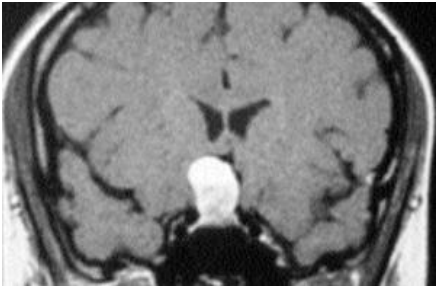

Observe a ressonância magnética, abaixo:

A imagem acima, indica, Cisto da bolsa de Rathke - RM com uso de gadolíneo, corte coronal. Observa-se massa hiperintensa, em T1 de crescimento: